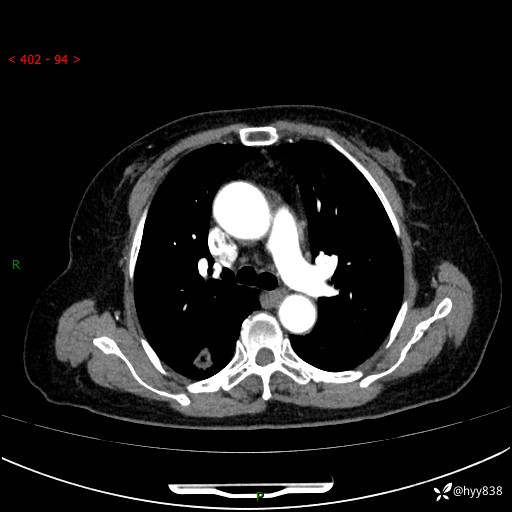

71岁/女,发现肺结节1月。偶然发现孤立肺结节,邻近叶间裂凹陷---结果公布(再回首)

【患者信息】:71岁/女

【主诉】:发现肺结节1月

【现病史及既往史】:2024年9月患者因“胆囊结石”于我院肝胆外科住院,期间完善胸部CT提示:右下肺结节灶,高危结节?感染?,病程中无畏寒发热,无咳嗽、咳痰,无活动后气短,无心慌胸闷,无胸痛、咯血,无头晕头痛,无腹痛腹泻,无四肢肌肉酸痛等不适,当时建议其择期复查。今日患者为求进一步复查就诊于我院,完善胸部CT提示:右肺结节,较前一致,遂门诊“肺部结节”收入我科。 自本次起病以来,患者精神、饮食、睡眠可,大小便正常,体力、体重未见明显异常。

【检查】:胸部CT平扫+增强